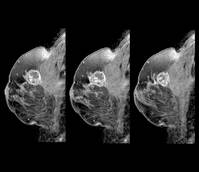

À¯¹æ¾Ï ȯÀÚ, Áõ»ó ¾ø¾îµµ ³ú ÀüÀÌ¡¦ ¡°MRI Á¶±â ¹ß°ß °¡..

[26/03/18 10:16]

¹«Áõ»óÀÌ´õ¶óµµ À¯¹æ¾Ï ÀϺΠ¾ÆÇü¿¡¼ ÁøÇ༺À̶ó¸é ³ú MRI Á¤±â °Ë»ç°¡ ÇÊ¿äÇÏ´Ù´Â ¿¬±¸°¡ ³ª¿Ô´Ù.ÇöÀç ±¹³»¿Ü¿¡¼ Åë¿ëµÇ´Â ÁøÇ༺ À¯¹æ¾Ï ȯÀÚ¿¡°Ô´Â ½Å°æÇÐÀû Áõ»óÀÌ ¾ø´Ù¸é Á¤±âÀûÀÎ ³ú MRI °Ë»ç¸¦ ±Ç°íÇϰí ÀÖ..